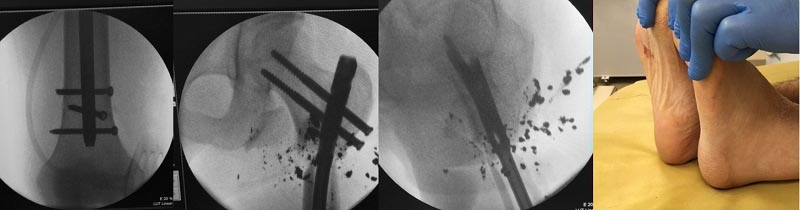

Уважаемые коллеги доброго времени суток! Поздравляю Вас с наступающим Новым Годом! Как обещал, отчитываюсь. С момента последнего сообщения - После первичной хирургической обработки и стабилизации перелома в АВФ ведения раны на VAC в течении 7 дней отделяемое из раны вызывало сомнение, проведена вторичная хирургическая обработка раны, удалены костные отломки которые даже частично были лишены надкостницы, инородные тела. С учетом поперечной линии излома торца проксимального отломка торец дистального отломка частично резецирован(тоже был лишен надкостницы). Повторный посев из раны , а/б терапия с учетом чувствительности, VAC терапия продолжена. На фоне проводимой терапии - рана активно гранулировала, контрольный посев из раны роста флоры не обнаружил. Сегодня пациент оперирован - остеосинтез стержнем LAFN. Репозицию выполнял в стержневом аппарате. Канал рассверлил. Рану ушил. Контроль интраоперационный в приложении. Комментарии, критика приветствуются. С уважением Леонид Пак